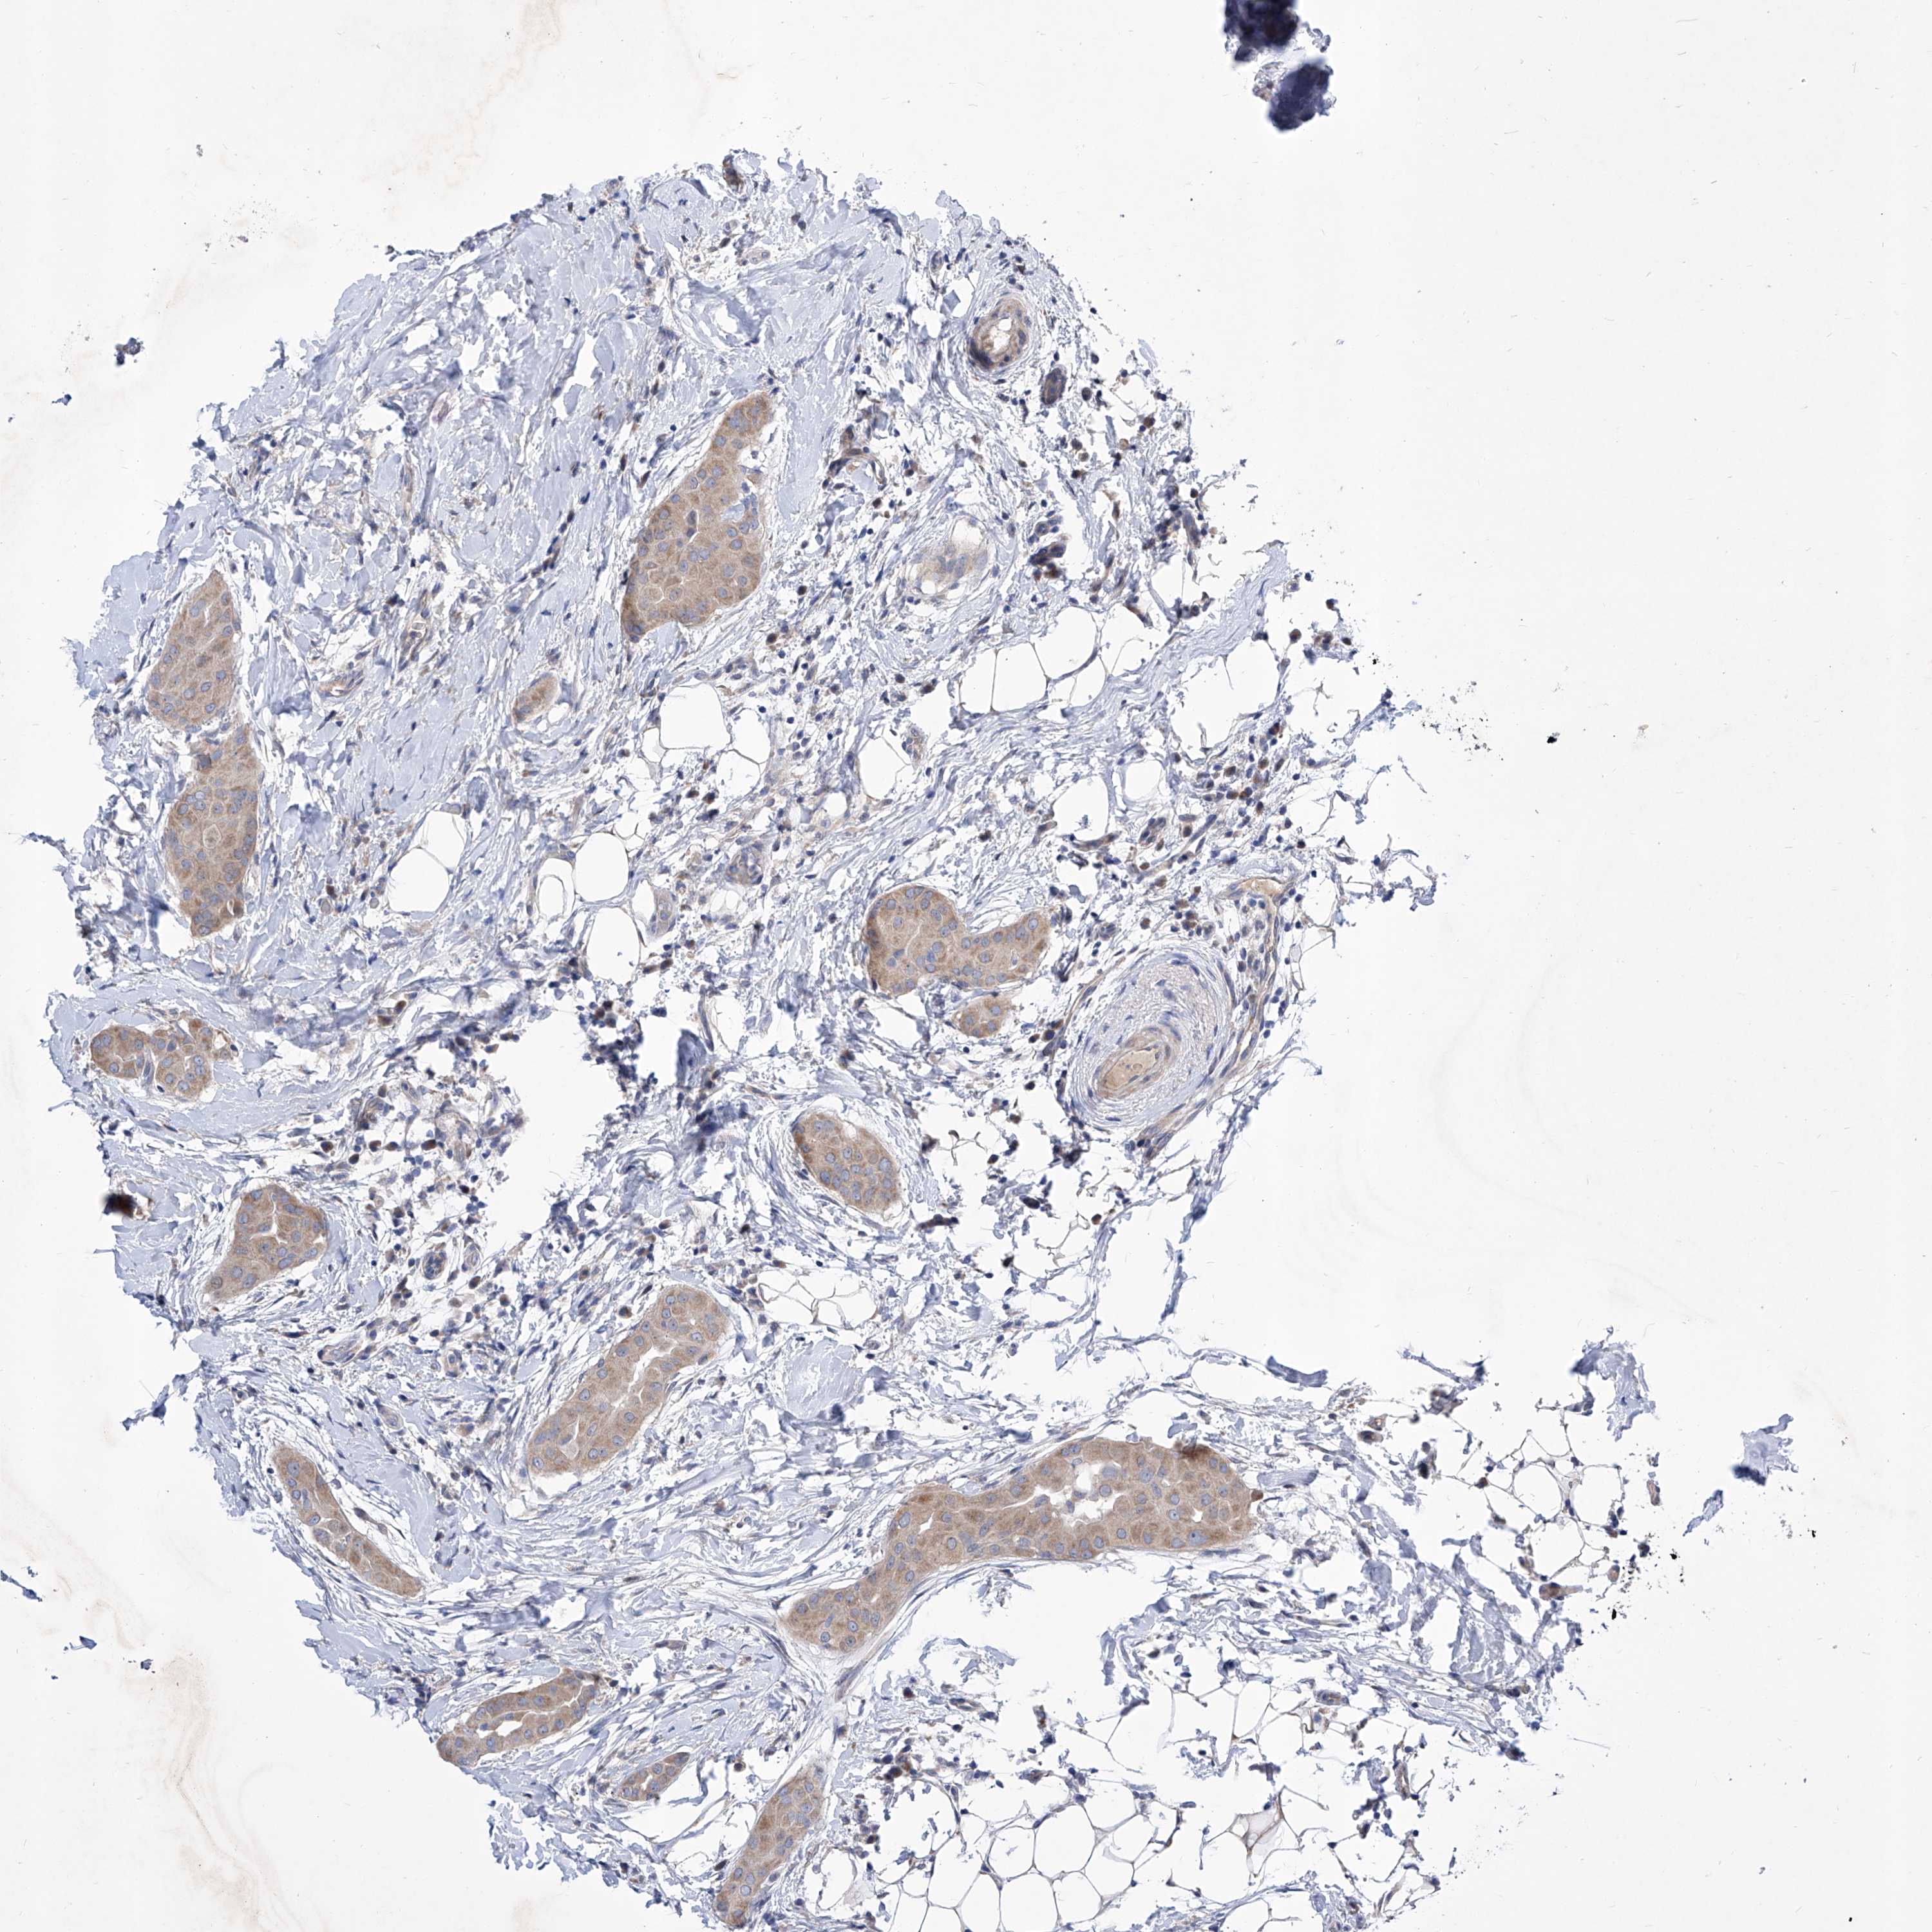

THYROID CANCER - Protein expressioni

A mouse-over function shows sample information and annotation data. Click on an image to view it in a full screen mode. Samples can be filtered based on level of antibody staining by selecting one or several of the following categories: high, medium, low and not detected. The assay and annotation is described here.

Note that samples used for immunohistochemistry by the Human Protein Atlas do not correspond to samples in the TCGA dataset.

Antibody stainingi

Antibody staining in the annotated cell types in the current human tissue is reported as not detected, low, medium, or high, based on conventional immunohistochemistry profiling in selected tissues. This score is based on the combination of the staining intensity and fraction of stained cells.

Each image is clickable and will lead to virtual microscopy that enables deeper exploration of all samples and also displays staining intensity scores, fraction scores and subcellular localization as well as patient and tissue information for each sample.

Antibody HPA030567

Antibody HPA030568

Staining

High

Medium

Low

Not detected

Intensity

Strong

Moderate

Weak

Negative

Quantity

>75%

75%-25%

<25%

None

Location

Nuclear

Cytoplasmic/membranous

Cytoplasmic/membranous,nuclear

Papillary adenocarcinoma, NOS

Follicular adenoma carcinoma, NOS